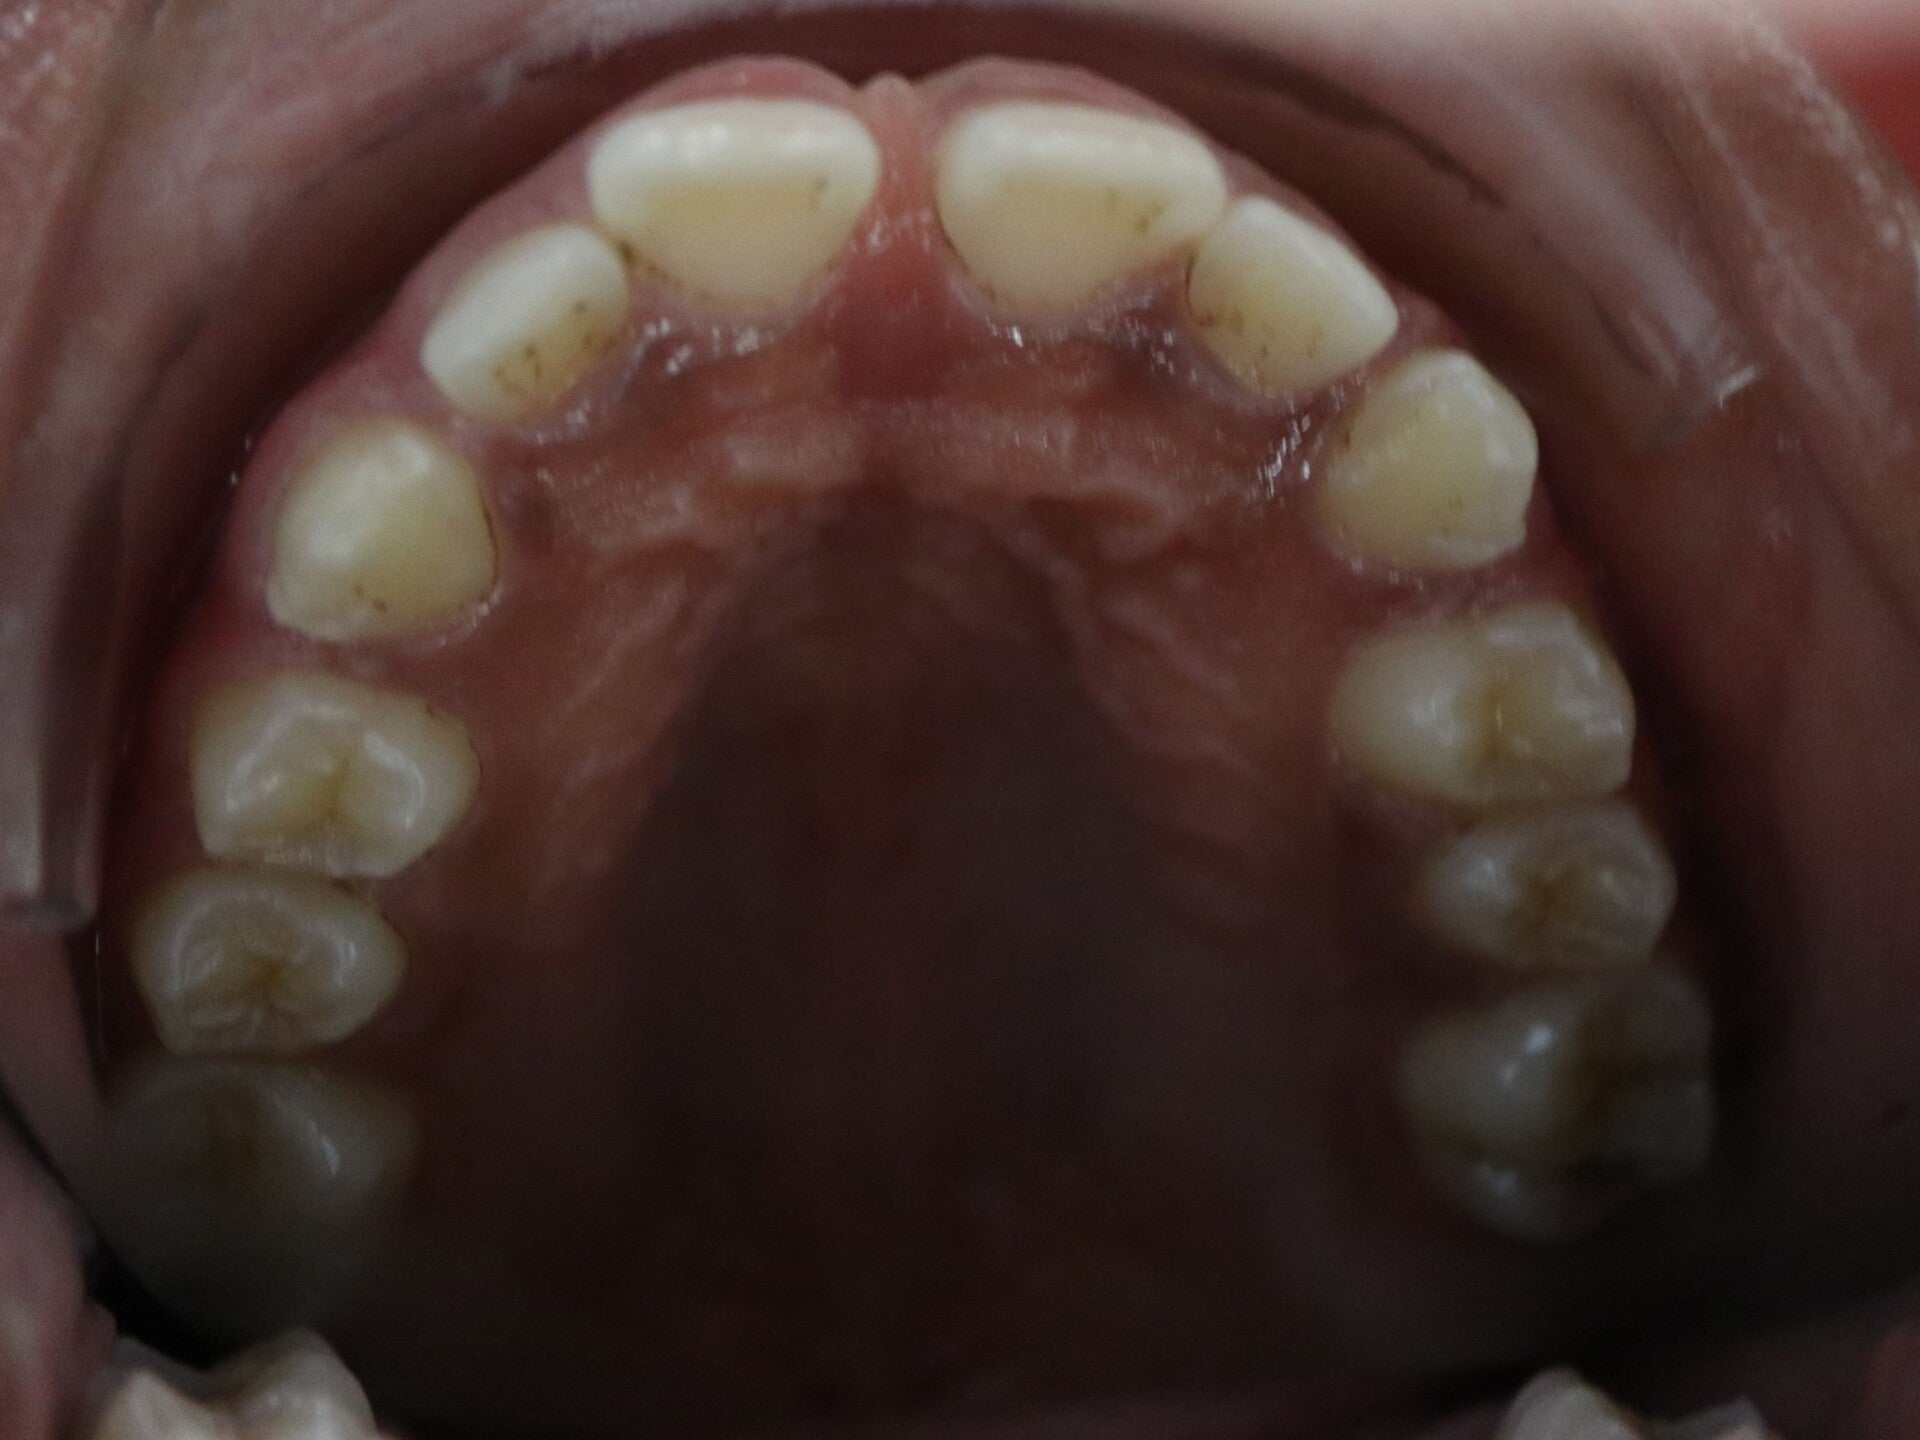

Occlusion inversée postérieure

Les dents du haut sont à l’intérieur des dents du bas